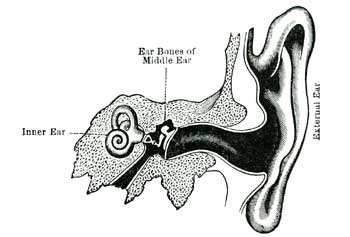

| XXV. | How we Hear, See, Smell, Taste; and Feel | 138 |